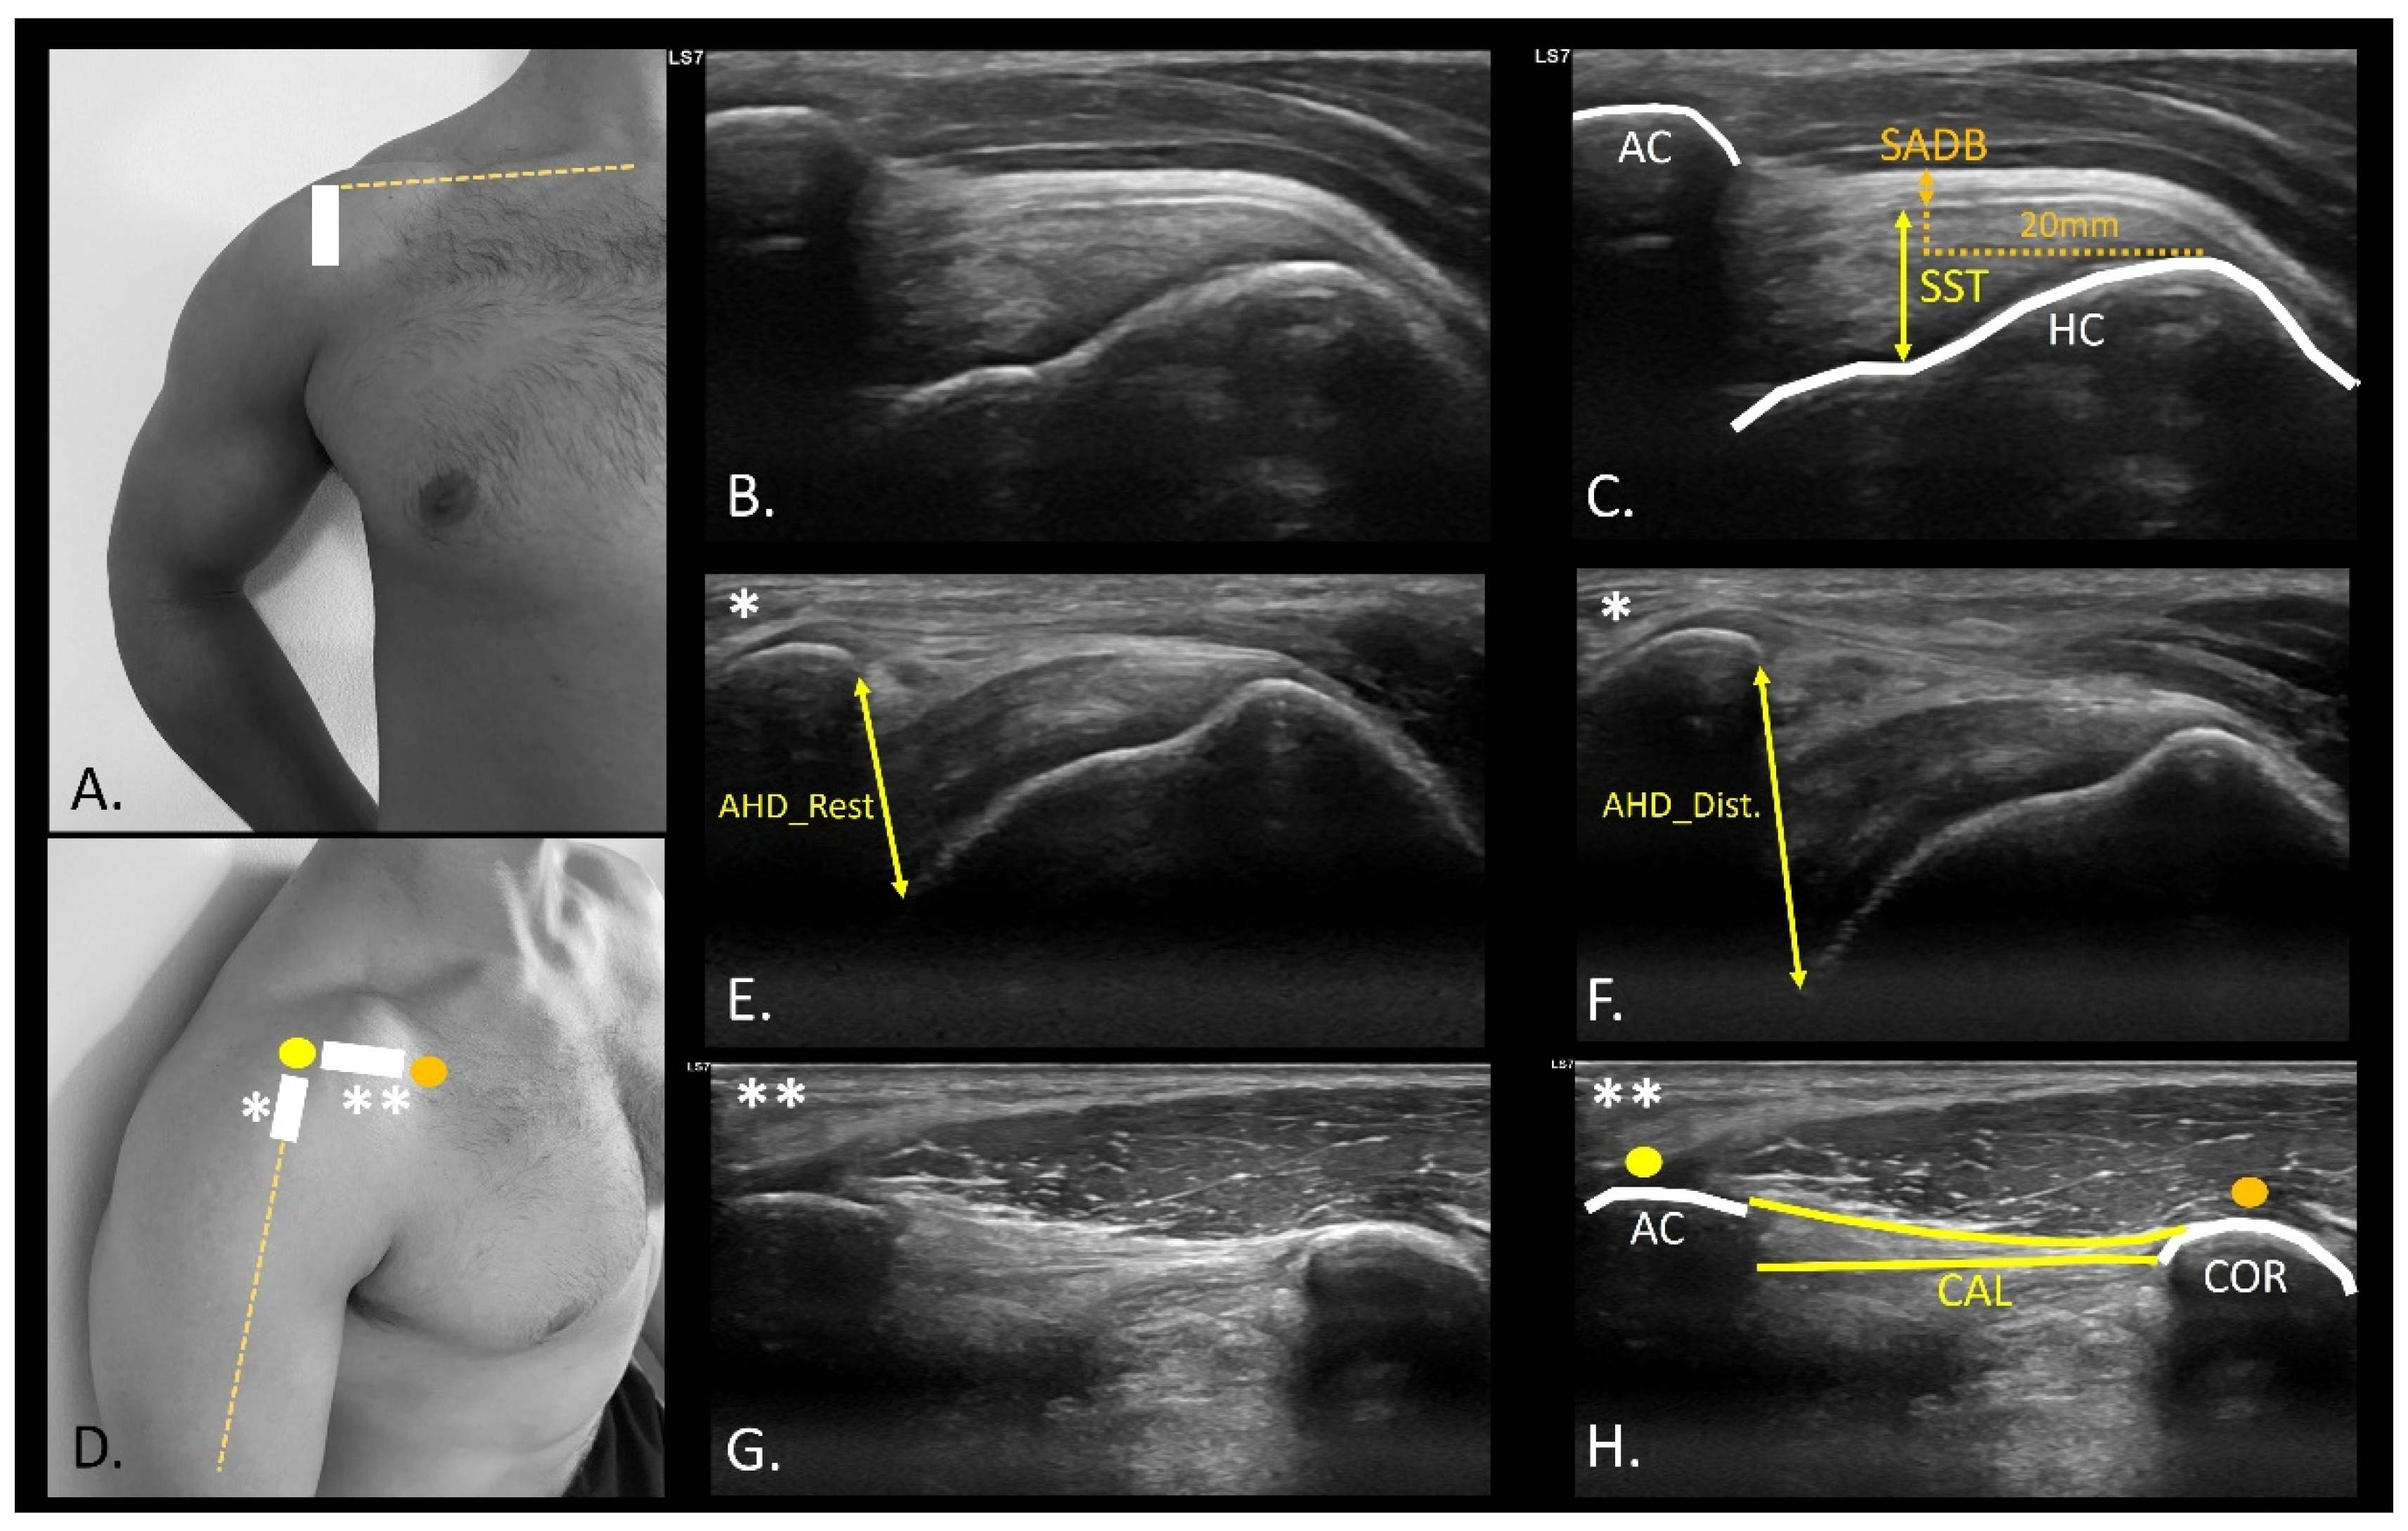

2.5. USI Assessment

- Hougs Kjær, B.; Ellegaard, K.; Wieland, I.; Warming, S.; Juul-Kristensen, B. Intra-rater and inter-rater reliability of the standardized ultrasound protocol for assessing subacromial structures. Physiother. Theory Pract. 2017, 33, 398–409. Available online: https://pubmed.ncbi.nlm.nih.gov/28481725/ (accessed on 14 July 2025). [CrossRef] [PubMed]

- Kjær, B.H.; de Wandele, I.; Spanhove, V.; Juul-Kristensen, B.; Cools, A.M. Subacromial space outlet in female patients with multidirectional instability based on hypermobile Ehlers-Danlos syndrome and hypermobility spectrum disorder measured by ultrasound. J. Shoulder. Elbow. Surg. 2020, 29, 600–608. [Google Scholar] [CrossRef] [PubMed]

- Dietrich, T.J.; Jonczy, M.; Buck, F.M.; Sutter, R.; Puskas, G.J.; Pfirrmann, C.W.A. Ultrasound of the coracoacromial ligament in asymptomatic volunteers and patients with shoulder impingement. Acta Radiol. 2016, 57, 971–977. [Google Scholar] [CrossRef] [PubMed]

- Miyake, S.; Tamai, M.; Takeuchi, Y.; Izaki, T.; Arashiro, Y.; Shibata, Y.; Shibata, T.; Yamamoto, T. Alteration of coracoacromial ligament thickness at the acromial undersurface in patients with rotator cuff tears. JSES Int. 2022, 6, 468. [Google Scholar] [CrossRef] [PubMed]

- Mazaleyrat, M.; Barthélémy, R.; Bouilleau, L.; Charousset, C.; Berhouet, J. Inter- and intra-observer reproducibility of ultrasound analysis of the long head of the biceps. Orthop. Traumatol. Surg. Res. 2020, 106, 235–239. [Google Scholar] [CrossRef] [PubMed]

- Cardoso, A.; Freire, G.; Alonso, R.; Afonso, P.D.; Pires, L. Bicipital groove cross-sectional area on ultrasonography: Does a correlation to intra-articular tendon pathology exist? Orthop. Traumatol. Surg. Res. 2021, 107, 102747. Available online: https://pubmed.ncbi.nlm.nih.gov/33333282/ (accessed on 16 July 2025). [CrossRef] [PubMed]

| SST (cm) | 0.62 ± 0.07 (0.45–0.73) | 0.60 ± 0.06 (0.44–0.70) | 0.02 (−0.01–0.04) | 0.136 (0.34) |

| AHD_Rest (cm) | 0.90 ± 0.9 (0.75–1.06) | 0.92 ± 0.12 (0.73–1.24) | −0.02 (−0.07–0.02) | 0.285 (0.24) |

| AHD_Dist. (cm) | 1.13 ± 0.21 (0.80–1.50) | 1.13 ± 0.24 (0.78–1.75) | −0.01 (−0.6–0.05) | 0.944 (0.02) |

| AHD_Dif. (cm) | 0.23 ± 0.17 (0.04–0.60) | 0.21 ± 0.16 (0.02–0.56) | 0.02 (−0.02–0.07) | 0.341 (0.21) |

| BBLHT CSA (cm2) | 0.11 ± 0.02 (0.08–0.16) | 0.12 ± 0.02 (0.08–0.16) | −0.01 (−0.2–0.01) | 0.177 (0.31) |

| BG (°) | 118.26 ± 8.17 (95.00–130.80) | 117.55 ± 10.66 (95.40–132.00) | 0.71 (−3.31–4.74) | 0.714 (0.08) |

| CAL distance (cm) | 2.89 ± 0.29 (2.16–3.36) | 2.82 ± 0.37 (2.05–3.77) | 0.002 (−0.04–0.16) | 0.231 (0.27) |

| CAL thickness (mm) | 1.01 ± 0.03 (0.26–1.64) | 1.02 ± 0.03 (0.59–1.69) | −0.0002 (−0.018–0.017) | 0.977 (0.006) |

| SADB thickness (mm) | 0.9 ± 0.53 (0.4–2.5) | 0.7 ± 0.43 (0.2–1.7) | 0.2 (0.07–0.32) | 0.004 (0.74) * |